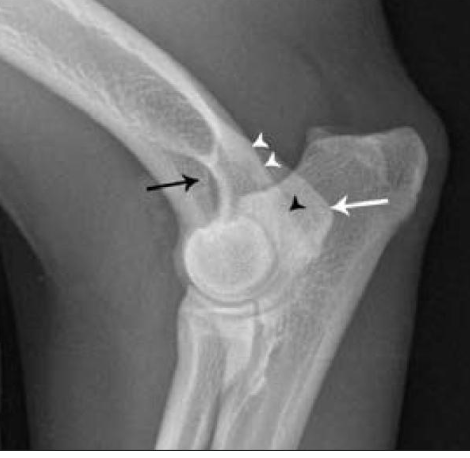

what is the red circle highlighting?

tricipital line present in the humerus

what is the orange circle highlighting?

deltoid tuberosity

where does the tricipital line of the humerus extend?

disto-cranially to merge with the deltoid tuberosity